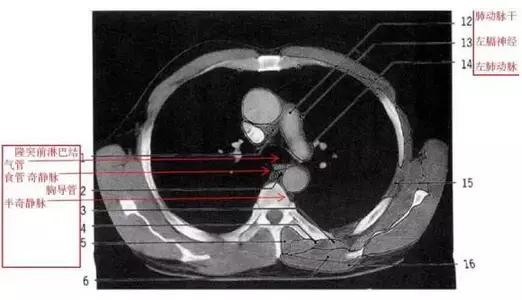

胸部的CT是通过X线计算机体层摄影(CT)对胸部进行检查的一种方法。正常胸部CT层面较多,每一层面结构所表现的图像不同。下面是胸部CT图文示意图,可帮助临床医生详细了解CT结构。我们一起来看一下吧。